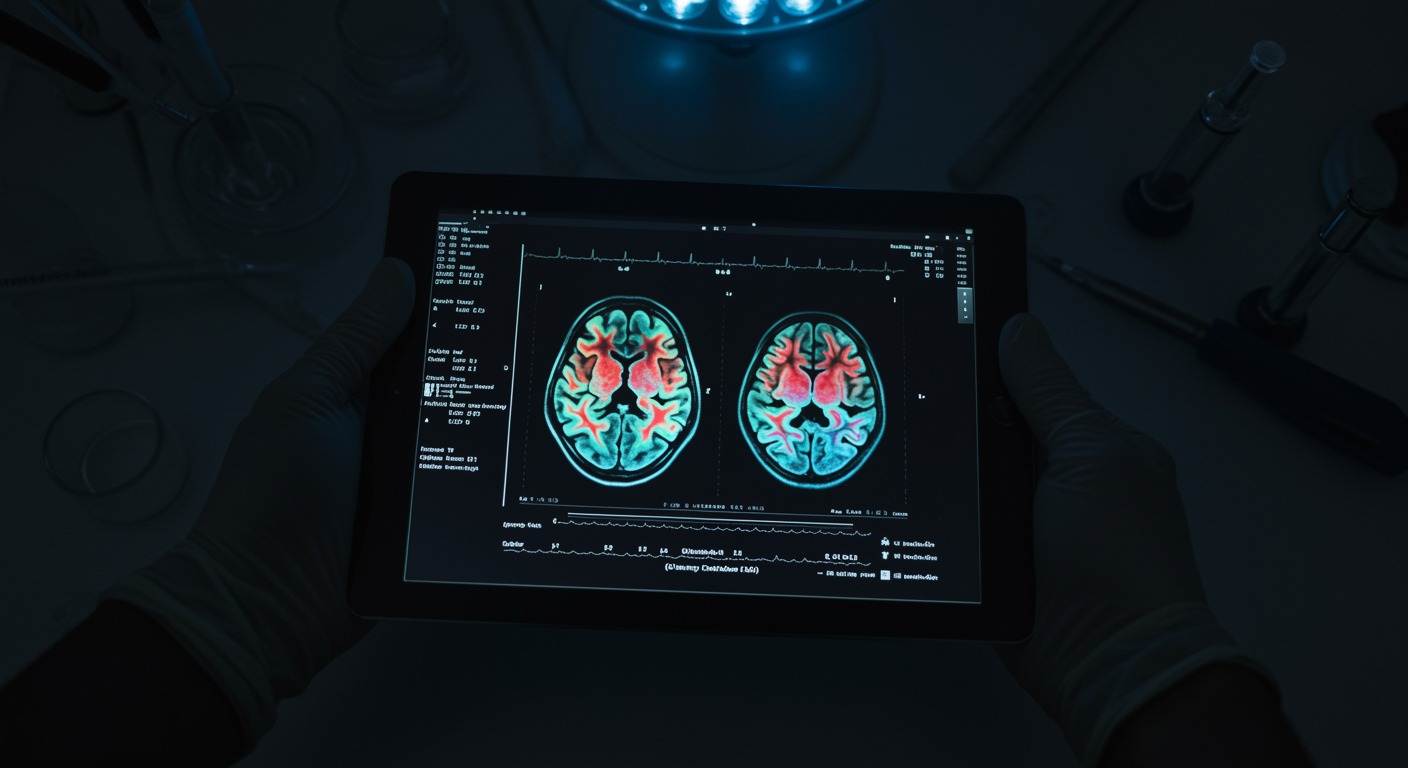

The nervous system—including the brain, spinal cord, and peripheral nerves—controls every function in the human body. From conscious thought and movement to subconscious regulation of bodily processes, neurologic health impacts every aspect of well-being.

- Cognitive Function: Understanding memory, focus, and executive function

- Neuroplasticity: The brain’s remarkable ability to reorganize and adapt

- Neuroinflammation: The role of inflammation in neurologic disorders